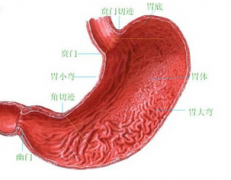

十二指肠球部溃疡的治疗

导读 十二指肠球部溃疡的主要临床表现为上腹部疼痛,可为钝痛、灼痛、胀痛

十二指肠溃疡有哪些症状,什么病因引起的

导语 十二指肠溃疡是消化科常见病之一,十二指肠任何部位都可发生溃疡,但

如何治疗十二指肠溃疡

导读 十二指肠溃疡是消化科常见病之一,十二指肠任何部位都可发生溃疡,但

十二直肠溃疡的症状

导读 十二指肠溃疡是消化科常见病之一,十二指肠任何部位都可发生溃疡,但 查看更多